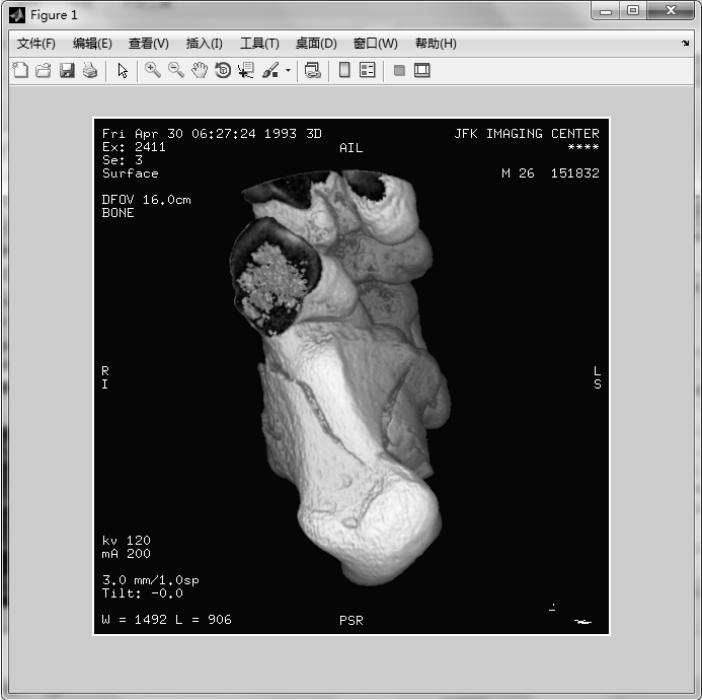

【实例2】 从DICOM元数据结构中读取图像数据。

图1.42 读取DICOM图像并创建10帧图像

图1.43 从DICOM元数据结构中读取图像数据